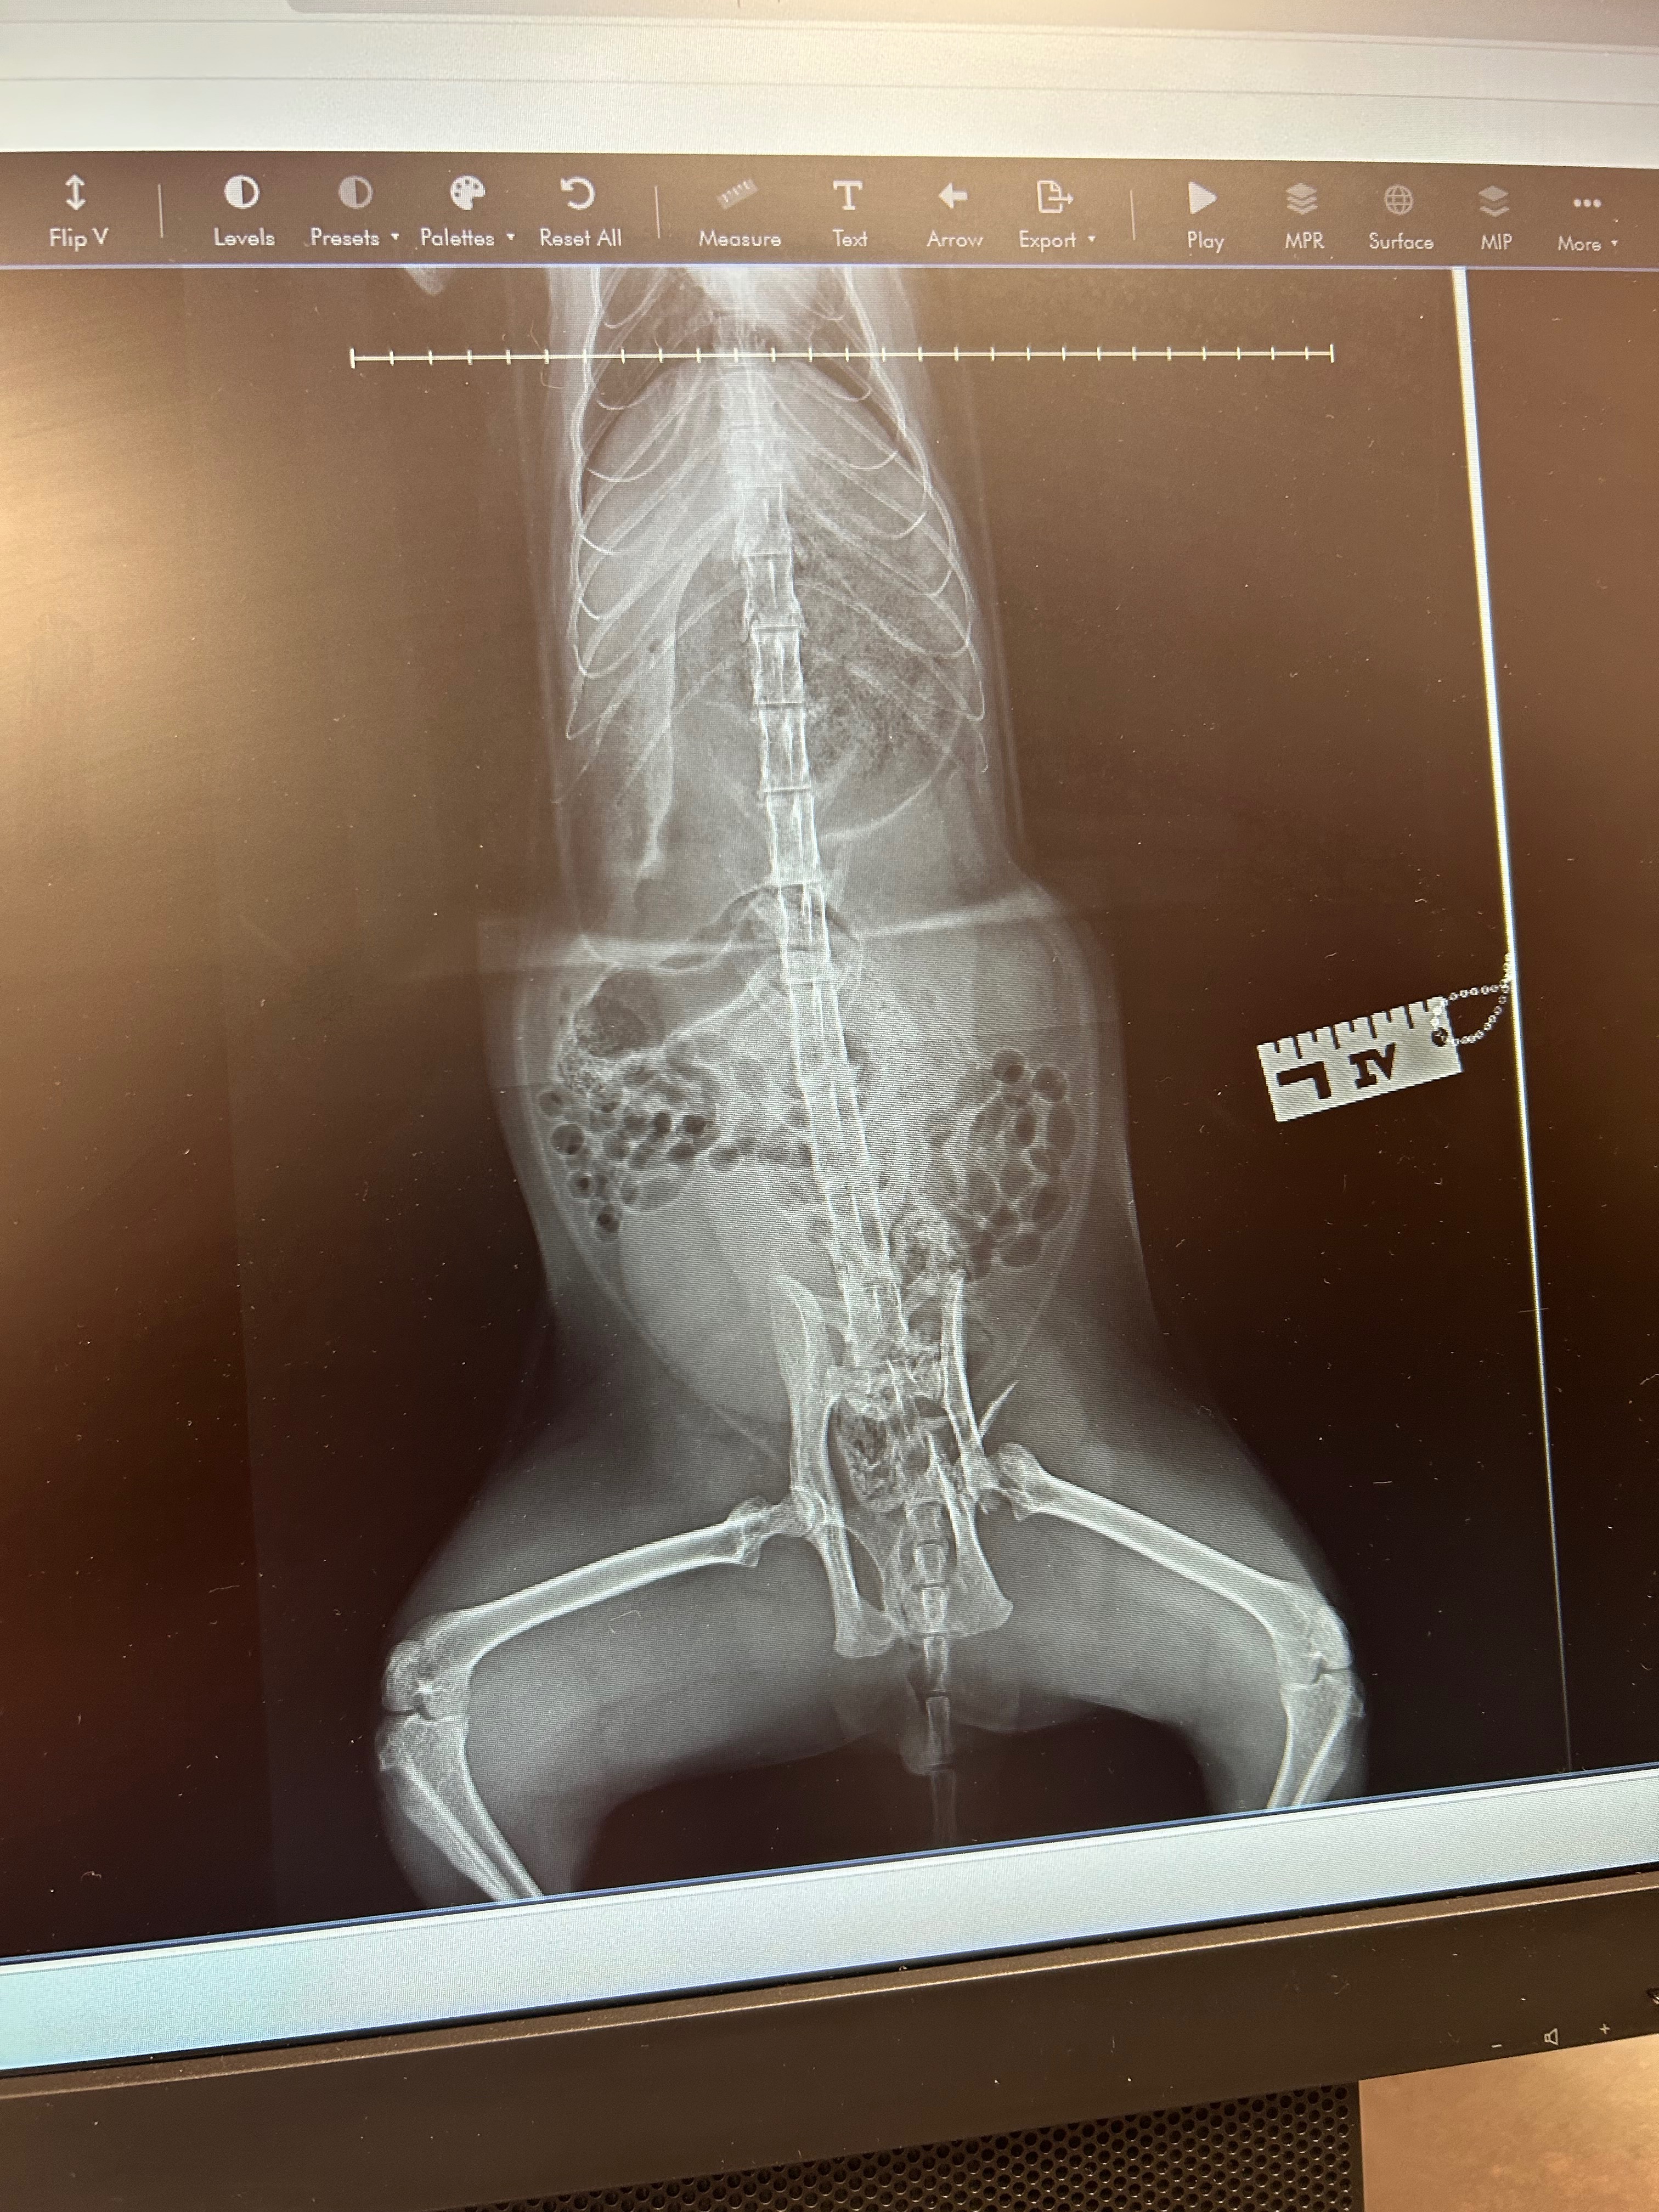

As you can see from the X ray, his pelvis is badly damaged on the left side and additionally he has a lung occlusion and laceration to his left cheek.

His pelvis is too badly damaged for reconstruction or prosthetics so will be the femoral head and neck excision. Praying for things to go well and he can go on and live a happy healthy life.